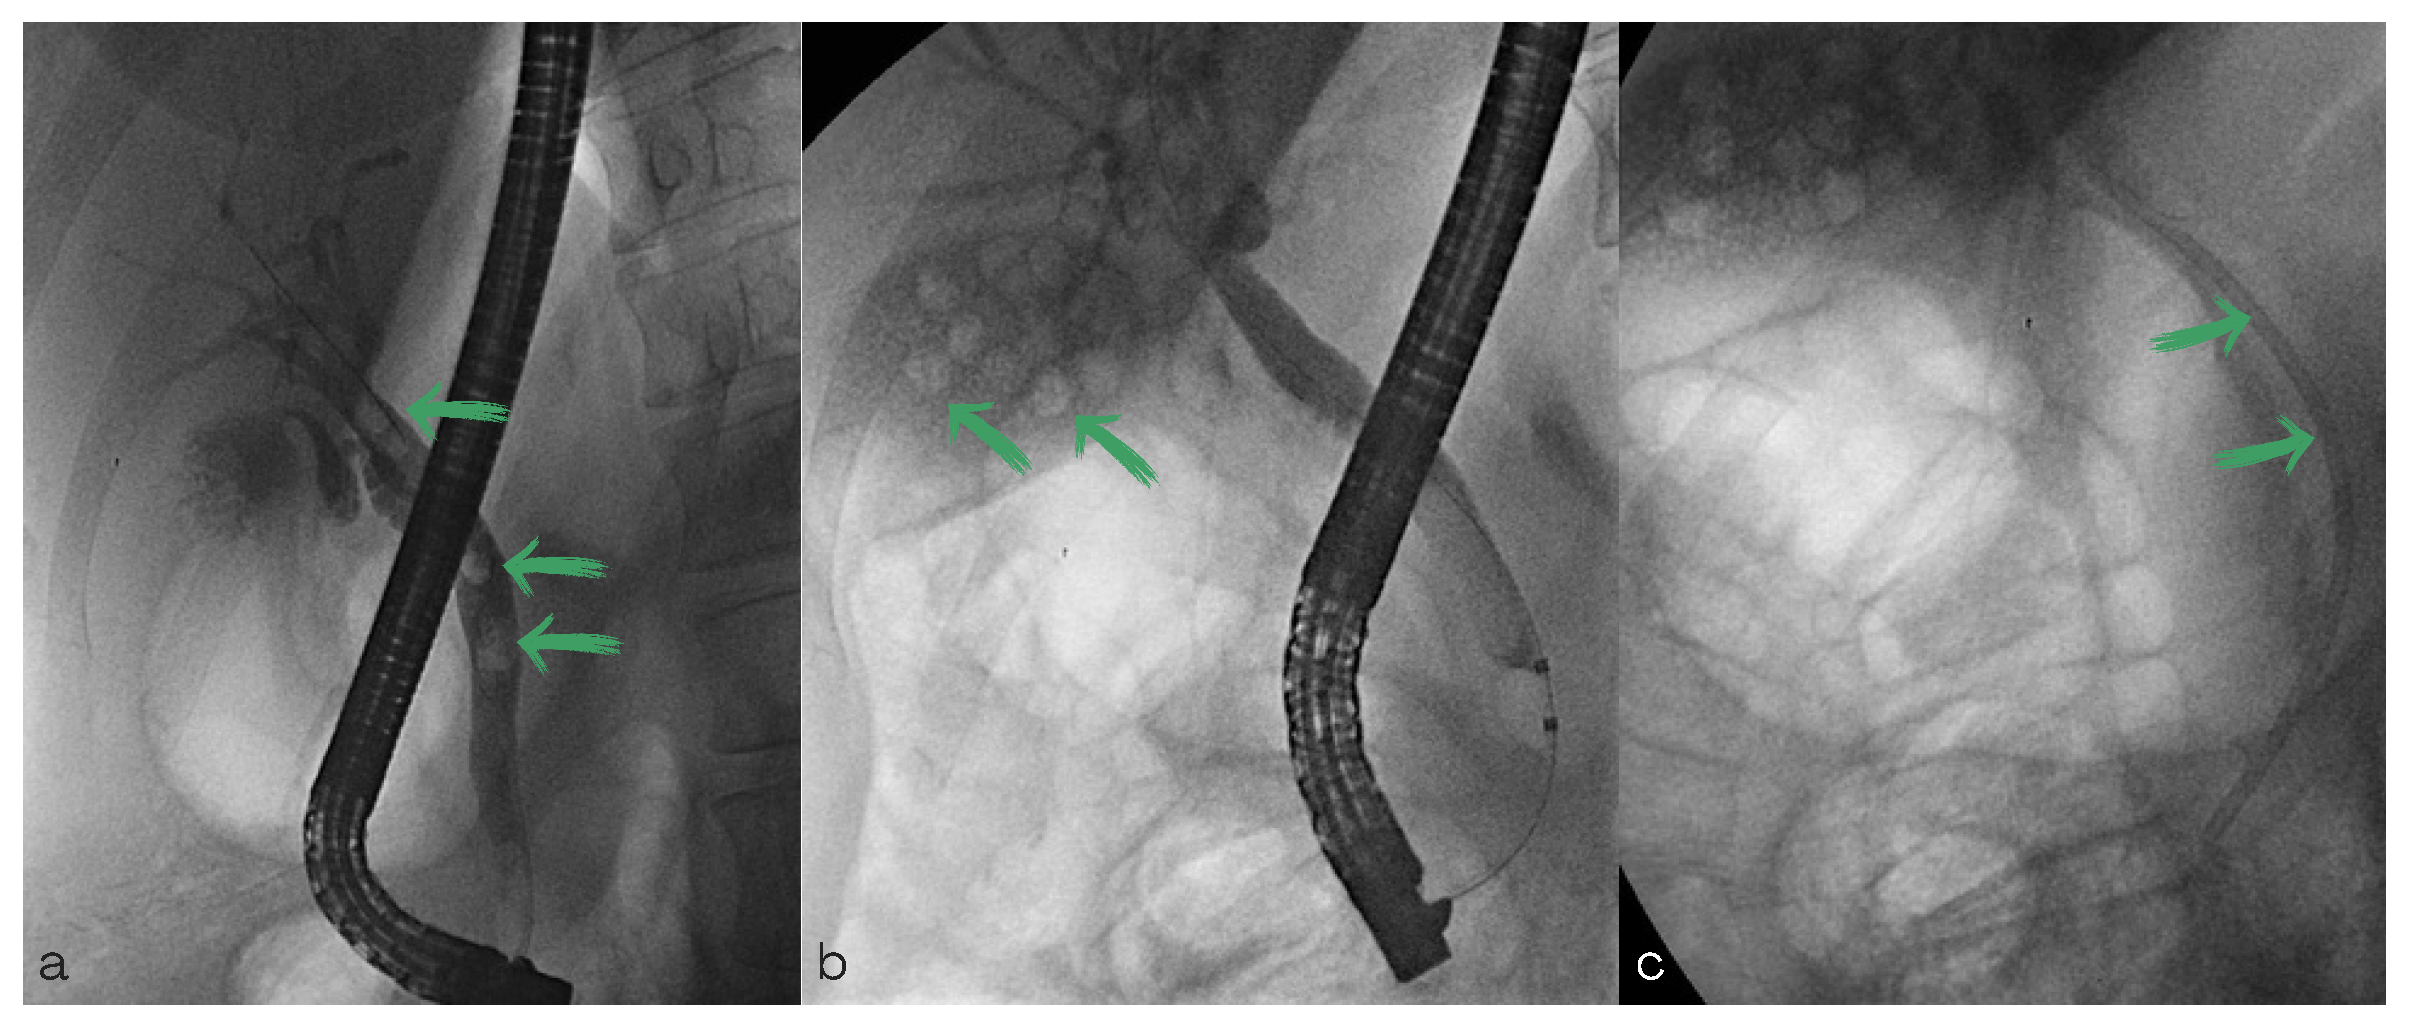

2. Case Report